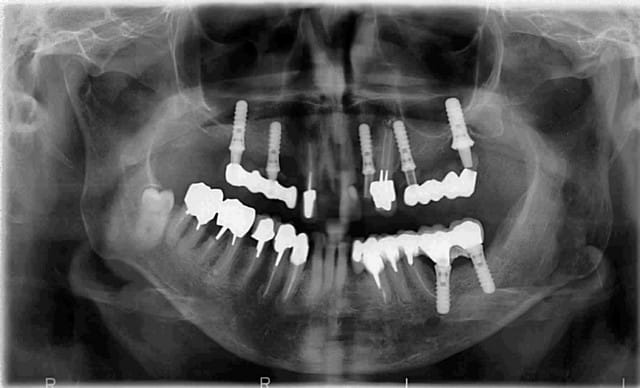

Voilà. Cette patiente se présente à moi. Elle est suivi depuis assez longtemps par un stomato. Qui l'a pris en charge pour la pose des implants que vous voyez sur la Pano.

Les implants maxillaire sont sous provisoires depuis au moins 8 mois. La dernière fois que j'ai vu la patiente je lui ai dit que l'on peut soir envisager un implant en position de 11, ou envisager un bridge 12-11-21 Car je pense que esthétiquement ce sera plus jouable...

intéressants, les implants zygomatiques qui s'arrêtent au quart du chemin. d'un point de vue biomécanique, ce traitement implantaire, c'est n'importe quoi. les édentements terminaux à droite et à gauche doivent être soutenus par 3 implants minimum, de préférence ostéo-intégrés, et de préférence pas dans la cavité sinusienne (il se peut que les implants soient placés dans une paroi sinusienne en évitant la cavité, mais je doute). la ligne de gencive sur l'implant en 22 est irrécupérable, car il n'y a rien pour soutenir une greffe. ce que je ferai:

1-examen scanner pour voire exactement ou se baladent ces implants.

2-dépose des implants douteux, je pense par exemple à l'implant distal à gauche.

pour moi, c'est condamné non seulement en haut à gauche mais aussi en bas à gauche...

en haut à droite, il y a trop peu d'implants et le bras de levier par rapport à l'axe implantaire est trop important...

secundo: tu ne peux arriver à t'en sortir au maxillaire pour une longue durée à moins de virer toutes les dents et de procéder à une greffe et ROG en haut à hauche après avoir déposé l'implant 27, et donc tu dois PLANIFIER les extractions dentaires, le placement des racines artificielles, la dépose de l'implant 27, la surélévation sinusale,plus la greffe d'apposition certainement nécessaire et la ROG associée...

tertio: quand l'infection anaérobique est maîtrisée, démonter les provisoires, effectuer un prélèvement ramique en bas à gauche (à conserver en liquide physiologique), lambeau bien disséqué (pour la fermeture) de 17 à 27 et LA TOTALE EN UNE SEANCE...avec extractions dentaires, pose des implants 15, 13, 12, 11, 21, 23, 25, vissage des vis de couverture (y compris celles des implants déjà posés), dépose de l'implant 27, sinus lift, greffe d'apposition, chips d'os tout autour et au-dessus des implants, membranes par dessus tout le bazar, fermeture hermétique, et la soupe pour un mois.